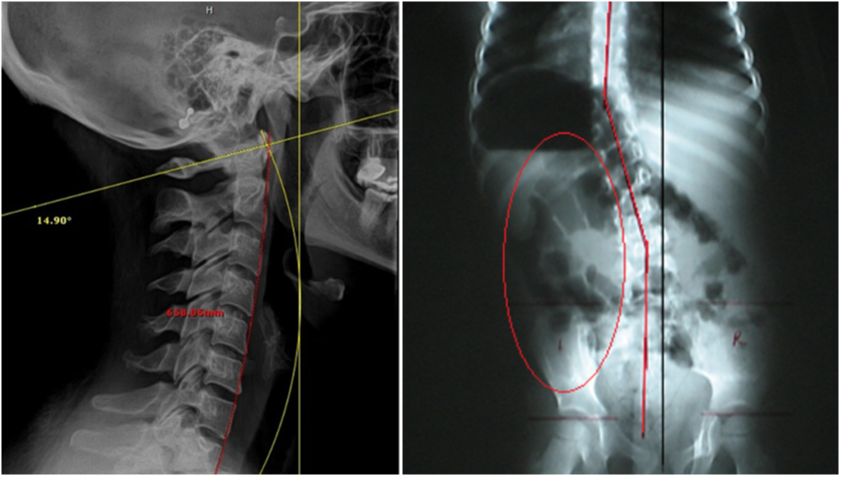

2. DIGITAL SPINAL RADIOGRAPHY

PRS also utilizes static X-ray, to provide precise, spinal alignment studies and rule out pathologies.

By providing a clear baseline for further diagnosis and care, static X-rays enable chiropractors to develop targeted strategies tailored to each patientâs needs.

Serving as the cornerstone for our more advanced technologies and techniques, this method ensures a solid starting point, empowering practitioners to build upon accurate data for optimal spinal correction and lasting patient outcomes.

4. SPINAL CORRECTION

You'll get a step-by-step walkthrough Pierce's proprietary subluxation correction method. The hallmark of our subluxation correction is the ability to prove that you've corrected your patient's problem.Â

Our peer-reviewed research shows that our system of spinal subluxation correction is supported by peer-reviewed research, which shows that it produces the fastest and most dramatic post x-ray changes within one to six visits.